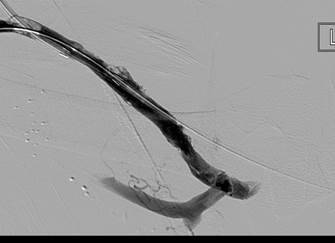

Fistulogram demonstrating thrombotic occlusion of a left brachiocephalic AV fistula (Note: arterial reflux of contrast).

Post 1st pass with AngioJet DVX Catheter (no thrombolytics used).

Post 2nd pass with DVX Catheter and balloon angioplasty of underlying stenosis. No impedance to forward flow in AVF.

Once forward flow is established and stenosis treated, the residual thrombus should resolve.